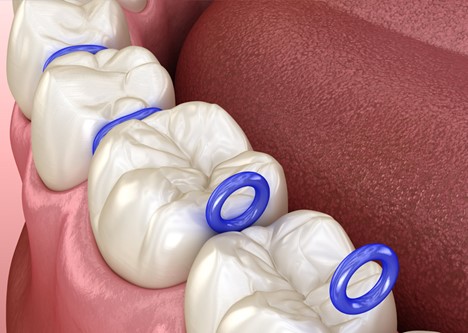

جدا کننده های ارتودنسی (که معمولاً به عنوان اسپیسر یا سپراتور شناخته می شوند) رابر بندها یا ابزارهای فلزی هستند که در ارتودنسی استفاده می شوند. سپراتورها در جلسه دوم ارتودنسی، قبل از اعمال بندهای دندان های مولر، بین دندان های مولر قرار داده می شوند. اسپیسرها یا رابر بندهای دایره ای به قطر حدود یک سانتی متر هستند که بین دندان های مولر بالا و پایین قرار می گیرند. ممکن است 1 تا 8 اسپیسر وجود داشته باشند یا گیره های فنری فلزی کوچک (جدا کننده های فنری) که دندان های مولر را از هم جدا می کنند. فاصله دهنده ها به مدت یک تا دو هفته بین دندان ها باقی می مانند و دندان ها را به آرامی از هم دور می کنند تا زمانی که به اندازه کافی از هم فاصله بگیرند تا ارتودنتیست ها بتوانند بریس های دندان ها یا بندهای دندان های مولر را بین آنها قرار دهند یا یک اکسپندر با حلقه های فلزی قرار دهند.

فرآیند قرار گیری اسپیسرها بین دندان ها معمولاً شامل کشیدن نخ دندانی است که از داخل سپراتور عبور داده شده است و قرار دادن سپراتور بین دندان ها است. برخی از اسپیسرها گیره های فنری فلزی کوچکی هستند که دندان ها را از هم جدا می کنند. در طول فرآیند مقداری فشار و بعد از آن مقداری درد وجود دارد، اما به طور کلی، فرآیند استفاده از اسپیسرها کاملاً بدون درد است، اگرچه ممکن است بیمار بلافاصله از فشار وارد شده به دندان ها احساس درد کند. گاهی اوقات بسته به فشردگی دندان ها از ابزارهای مخصوص ارتودنسی برای باز کردن کش ها استفاده می شود. اگر بخصوص دندان های قوس دندانی فشرده باشند، اسپیسرها ممکن است به دلیل نزدیک تر شدن بیشتر دندان ها باعث درد شدید دائمی شوند. این درد مدتی پس از قرار دادن شروع می شود و معمولاً چند روز طول می کشد.